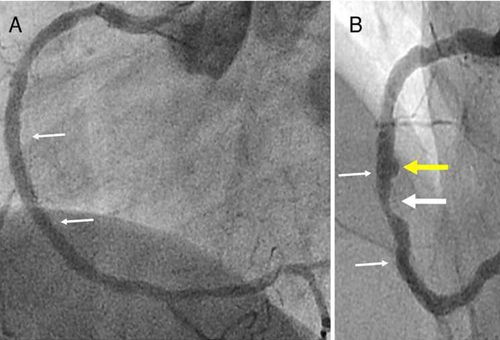

目前檢測冠心病有兩種手段,一是冠脈CT檢查,二是冠脈造影檢查。

冠脈CT是在患者手臂靜脈輸入對比造影劑,然后再進行心臟掃描,檢查可能存在的冠狀動脈病變。目前,雖不推薦將冠脈CT作為查體必備項目,但對于有患冠心病的高危人群,這項檢查是非常適合的,它無創(chuàng)準確,方便快捷,用于冠心病的初步篩查和冠脈血管評估。

對于這兩個檢查,很多病人會問:“這兩個檢查到底有什么區(qū)別?”其實冠脈CT就像平時輸液一樣在患者手臂的靜脈里輸入對比造影劑,然后對心臟進行掃描,借以尋找可能存在的冠狀動脈病變??旖莘奖?,準確性也高,患者接受起來比較容易。而冠脈造影屬于有創(chuàng)檢查且需住院,穿刺時還要局麻。但冠脈造影不僅可以明確診斷有無冠心病,而且可了解病變的部位、范圍及嚴重程度,還可同時進行支架介入治療,是冠脈CT檢查無法取代的。但不是所有的患者都適合做冠脈造影,嚴格聽從醫(yī)生的建議很重要。